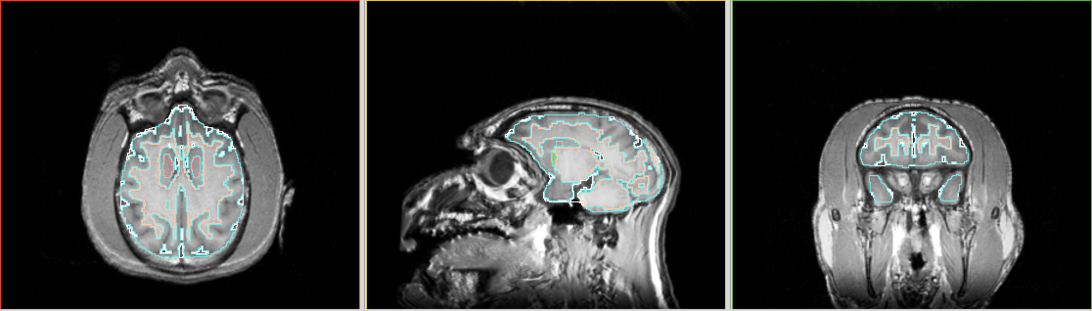

Segmentation results as in screen shots

View 2 : upper row - using Slicer 3.4 binary release; middle row - Slicer 3.4 build from source; lower row - using Slicer 2.6